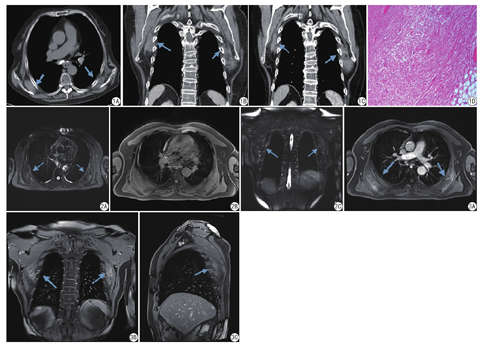

20例患者中,13例病灶位于双侧,4例病灶位于右侧,3例病灶位于左侧,CT共发现33处病灶,并均位于背部肩胛下角肌肉深面,均呈扁丘状或半圆形肿块,主要以肌肉样密度为主,病灶内见条纹状脂肪密度沿病灶长轴间隔排列;病灶边缘毛糙不整,周围脂肪间隙模糊不清,CT增强扫描3例轻度强化,5例无强化;EFD与前锯肌、EFD与周围脂肪间平扫及增强CT值差异均存在统计学意义(P<0.05);MRI平扫信号不均匀,呈等信号为主的肌组织与高信号的脂肪组织交错排列,MRI增强扫描1例呈不均匀中度强化。

20例患者CT共发现33处病变,其中13例病灶位于双侧,4例病灶位于右侧,3例病灶位于左侧,双侧发病率为65% (图1A)。肿块均以类似骨骼肌肉样密度为主,肿块均位于背部肩胛下角区背阔肌、前锯肌及菱形肌的深面,肋骨和肋间肌外侧脂肪间隙内,呈扁丘状,内部含有不同程度的脂肪成分,脂肪成分排列成间隔条状,与肿块长轴平行,肿块以宽基底位于胸肋侧,临近前锯肌、背阔肌及部分菱形肌不同程度受压移位,肿块内侧肋骨骨质完整。冠状位重建图像能更清楚地显示肿块与周围组织结构的关系。8例患者16个病灶行CT增强扫描,3例患者6个病灶轻度强化,5例患者10个病灶未强化(图1B、图1C)。对病灶与邻近前锯肌间、病灶与周围脂肪间平扫CT值及增强CT值分别进行比较(表1,表2),P值均小于0.05。说明无论CT平扫或增强检查,病灶与前锯肌、病灶与周围脂肪之间CT值差异均存在统计学意义。

4例患者6个病灶行MRI平扫检查,其中1例同时行增强检查,双侧2例,右侧1例,左侧1例,病灶均表现为以骨骼肌信号为主,内可见间隔状排列的条状长T2信号(图2A),脂肪抑制成像T1WI及T2WI脂肪高信号被抑制成低信号(图2B、图2C),说明为脂肪成分,增强后均呈不均匀中度强化(图3)。

术中见肿块位于肩胛下区背阔肌、前锯肌和菱形肌深部,无包膜,与周围肌肉组织分界不清,表面覆盖脂肪组织,基底位于胸肋侧,临近肋骨和肋间肌;切面呈灰白与淡黄色灶状颗粒相间,质韧。镜下见大量粗大弹力纤维及束状胶原纤维,并见灶状分布的脂肪组织,HE染色弹力纤维呈粉红色(图1D)。